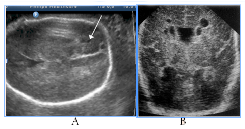

Among of infection-associated echographic signs of the fetal brain anomalies (for CMV, maternal VIH/AIDS, also unclassified etiology of neuroinfection) there were revealed changes, mainly of the intraventricular, subependymal and periventricular localization (Figure 11) (Figure 12) subependymal cysts, heterogeneous periventricular echogenicity, intraventricular adhesions, antenatal intraventricular haemorrage, hydrocephalus, cerebral edema signs, cystic PVL and signs of disgenetic processes - partial agenesis of the corpus callosum and cortical dysplasia.

Figure 11Infection-associated fetal brain abnormalities (neuroinfection of unknown etiology), two cases.

Figure 12Infection-associated fetal brain abnormalities (maternal VIH/AIDS), fetal NSG and postnatal MRI scans.

Figure 11 Infection-associated fetal brain abnormalities (neuroinfection of unknown etiology), two cases: A) Hydrocephalus, partial agenesis of the corpus callosum and subependymal cyst, infant death in 5 months. B) Intraventricular adhesion, adverse CPO.

Figure 12 Infection-associated fetal brain abnormalities (maternal VIH/AIDS), fetal NSG and postnatal MRI scans. A) Significant fetal hydrocephalus with a total extension of the ventricular system, cystic PVL (arrow). B) MRI after birth, cystic lesions on both sides of the shell, progressive internal and external hydrocephalia. Neonatal death.